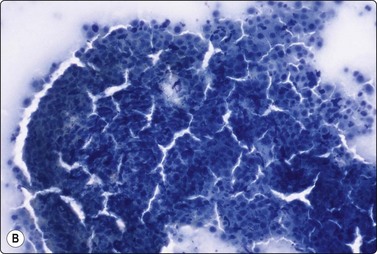

Yolk sac tumor (Figs 13.37 and 13.38)14,53-56,59-61,63

image image

Fig. 13.37 Endodermal sinus tumor

(A) Polypoid epithelial fragment of large malignant cells with pale, almost clear, vacuolated cytoplasm (MGG, HP); (B) Corresponding tissue section (H&E, IP).

Fig. 13.38 Endodermal sinus tumor

(A) A glomeruloid cell cluster with vacuolated cytoplasm on a mucoid background (DQ, IP); (B) Cell cluster with a vascular stalk and several hyaline globules.

Criteria for diagnosis

Mucoid background,

Glomeruloid structures,

Schiller-Duval bodies (characteristic finding when present),

Very immature cells, prominent nucleolus, basophilic cytoplasm,

Small naked nuclei,

Intra- or extracellular PAS-positive hyaline globules (AFP positive),

Prominent cytoplasmic vacuoles and distinct cell boundaries confer a clear-cell appearance,

Immunocytochemistry: focal staining for AFP, AE1/AE3 and PLAP; negative for OCT image.

Pure yolk sac tumors are almost always encountered in infants and young children but rare in the first 6 months of life.49 In adults, this pattern is seen in approximately 40% of nonseminomatous GCT;12 however, it can easily be mistaken for embryonal carcinoma in FNA smears. This is why most reported cases are of metastatic tumors. Hyaline globules and eosinophilic membrane-like material are hints to the diagnosis of this tumor type (Fig. 13.38B). In infants and young children, the aforementioned cytological criteria permit a confident diagnosis by FNA.